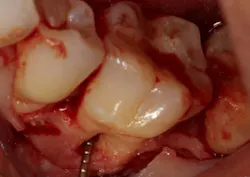

Another advancement in the field of periodontal regenerative medicine has been due to the use of growth factors, proteins, and stem cells. The ability to repair/regenerate a diseased tooth is often dependent upon the extent of the defect, namely the number of bone walls that are left surrounding the tooth. The more bone walls a tooth has left around it (maximum of four), the more blood supply, containment, and space maintenance your graft material will have (figure 5). Bone defects that have three to four walls missing are the hardest to repair and may be slated for extraction (figure 6). By adding growth-stimulating factors to your regular bone grafts (figure 7), an increase in osteopromotive potential occurs that can have the ability to overcome a deficiency of bone walls. (15) Simply stated, your bone graft can become alive, and teeth that were once unable to be repaired now have a chance.

Figure 6: Molar tooth with three walls missing around the palatal root. This tooth would normally be extracted.

Figure 7: Same tooth undergoing periodontal regeneration surgery with anorganic bovine bone (Bio-Oss Collagen, Geistlich Biomaterials) and platelet-derived growth factor (PDGF)